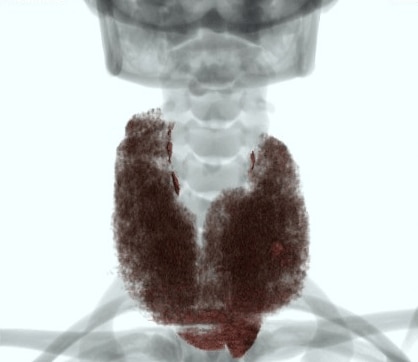

下記症例は19歳女性、甲状腺摘出術前で甲状腺容量測定の依頼があり、従来のCT装置では、Dual Energy撮影が出来なかったため、管電圧120kVで撮影していましたが、甲状腺の辺縁が同定しにくく、辺縁をトレースするのに苦労していました。Revolution CTが導入され、Dual Energy撮影が可能となり、低keVの画像を使用することで、甲状腺のCT値が上昇し境界が明瞭になり、容量測定が容易になりました。

VR画像